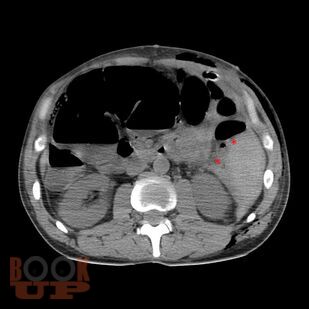

Учебно-методическое пособие посвящено проблемам лечения открытых и закрытых повреждений живота. Представлены классификации и характеристики ран, их современная диагностика, а также виды оперативных вмешательств при различных видах повреждений живота. Издание иллюстрировано рисунками, таблицами, имеются тестовые задания и задачи. Пособие предназначено для ординаторов, обучающихся по специальности 31.08.67 Хирургия и слушателей дополнительного профессионального образования.